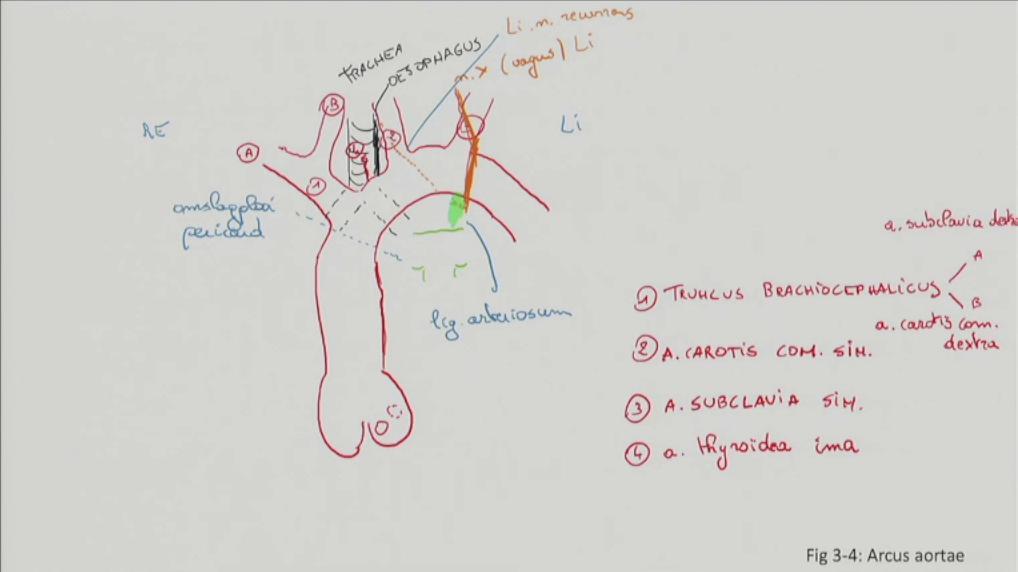

Fig 3.04: Arcus aortae

omslagplooi pericardium trachea esophagus tr. pulmonalis lig. arteriosum isthmus aortae (vernauwing lumen t.h.v. lig. arteriosum) linker n vagus (X) -

linker n vagus > linker n laryngeus recurrens = n recurrens

zijtakken arcus aorta

-

tr. brachiocephalicus

a subclavia dextra a carotis communis dextra

a carotis communis sinistra a subclavia sinistra (a thyroidea ima)